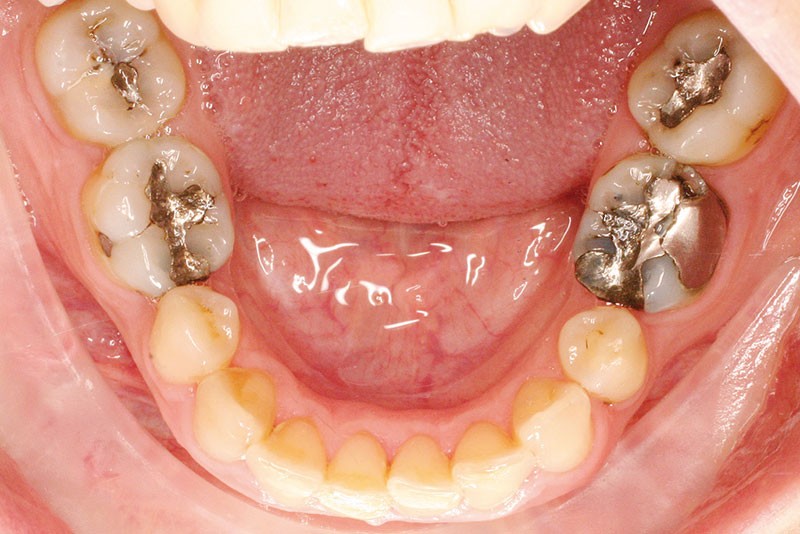

La patiente, âgée de 30 ans, présente des agénésies multiples : 12, 22, 14, 15, 24, 25, 35 et 45 (fig. 1 à 3).